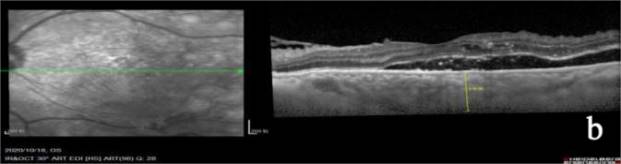

a:患者术前OCT,脉络膜厚度约398 μm,黄斑区形态大致正常;b:术后2天,脉络膜厚度约426 μm,后极部颞下方视网膜下少量积液,累及黄斑区,产生渗出性视网膜脱离;c:术后一周,脉络膜厚度约387 μm,后极部颞下方视网膜下积液吸收,黄斑区形态大致正常。

Figure 2. Variations in OCT at distinct preoperative and postoperative time intervals in patients with exudative retinal detachment

2. 渗出性视网膜脱离患者术前及术后不同时间点的OCT变化

有1只眼出现了渗出性视网膜脱离,我们分析原因有以下几点。1) 患者糖尿病病史20年,脑卒中病史15年,血糖控制欠佳,糖化血红蛋白为14%,术后反应较重,导致产生视网膜下积液。2) 患者新生血管增殖活跃,结合患者的全身情况,在顶压器辅助下扩大了激光光凝的范围、增加了光凝的数量,进一步加重了患者的术后反应。3) 玻璃体切割术后一般不给予全身使用激素控制炎性反应,增加了术后出现渗出性视网膜脱离的可能性[10]。患者未行特殊处理,于手术后1周完全吸收视网膜下积液。